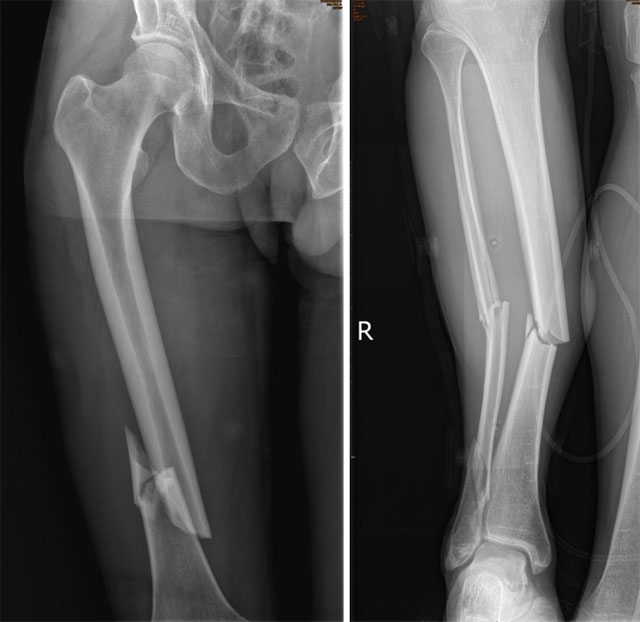

【围观】大腿、小腿3根骨头摔得“稀巴烂”

2023年3月31日,王先生被重物砸伤右下肢,当即出现右下肢疼痛、活动受限,随即联系西南医科大学附属中医医院骨伤科创伤·正骨组,科室手术团队严阵以待,做好紧急救治准备。全身多处骨折,出血过多出现失血性休克术前x线 完善X线等相关检查提示:右...